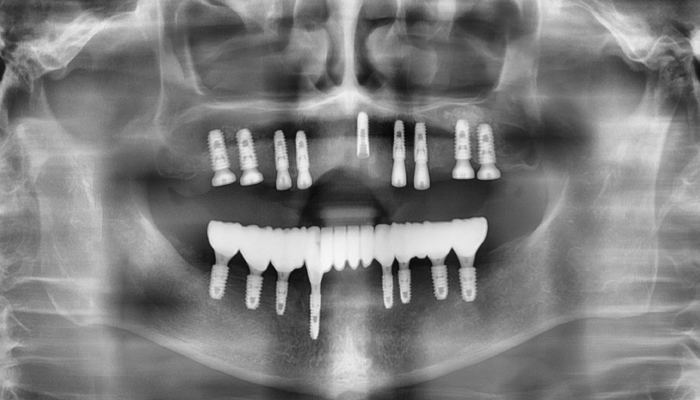

뼈이식 임플란트 전후 사례

• 식립 전

식립 후